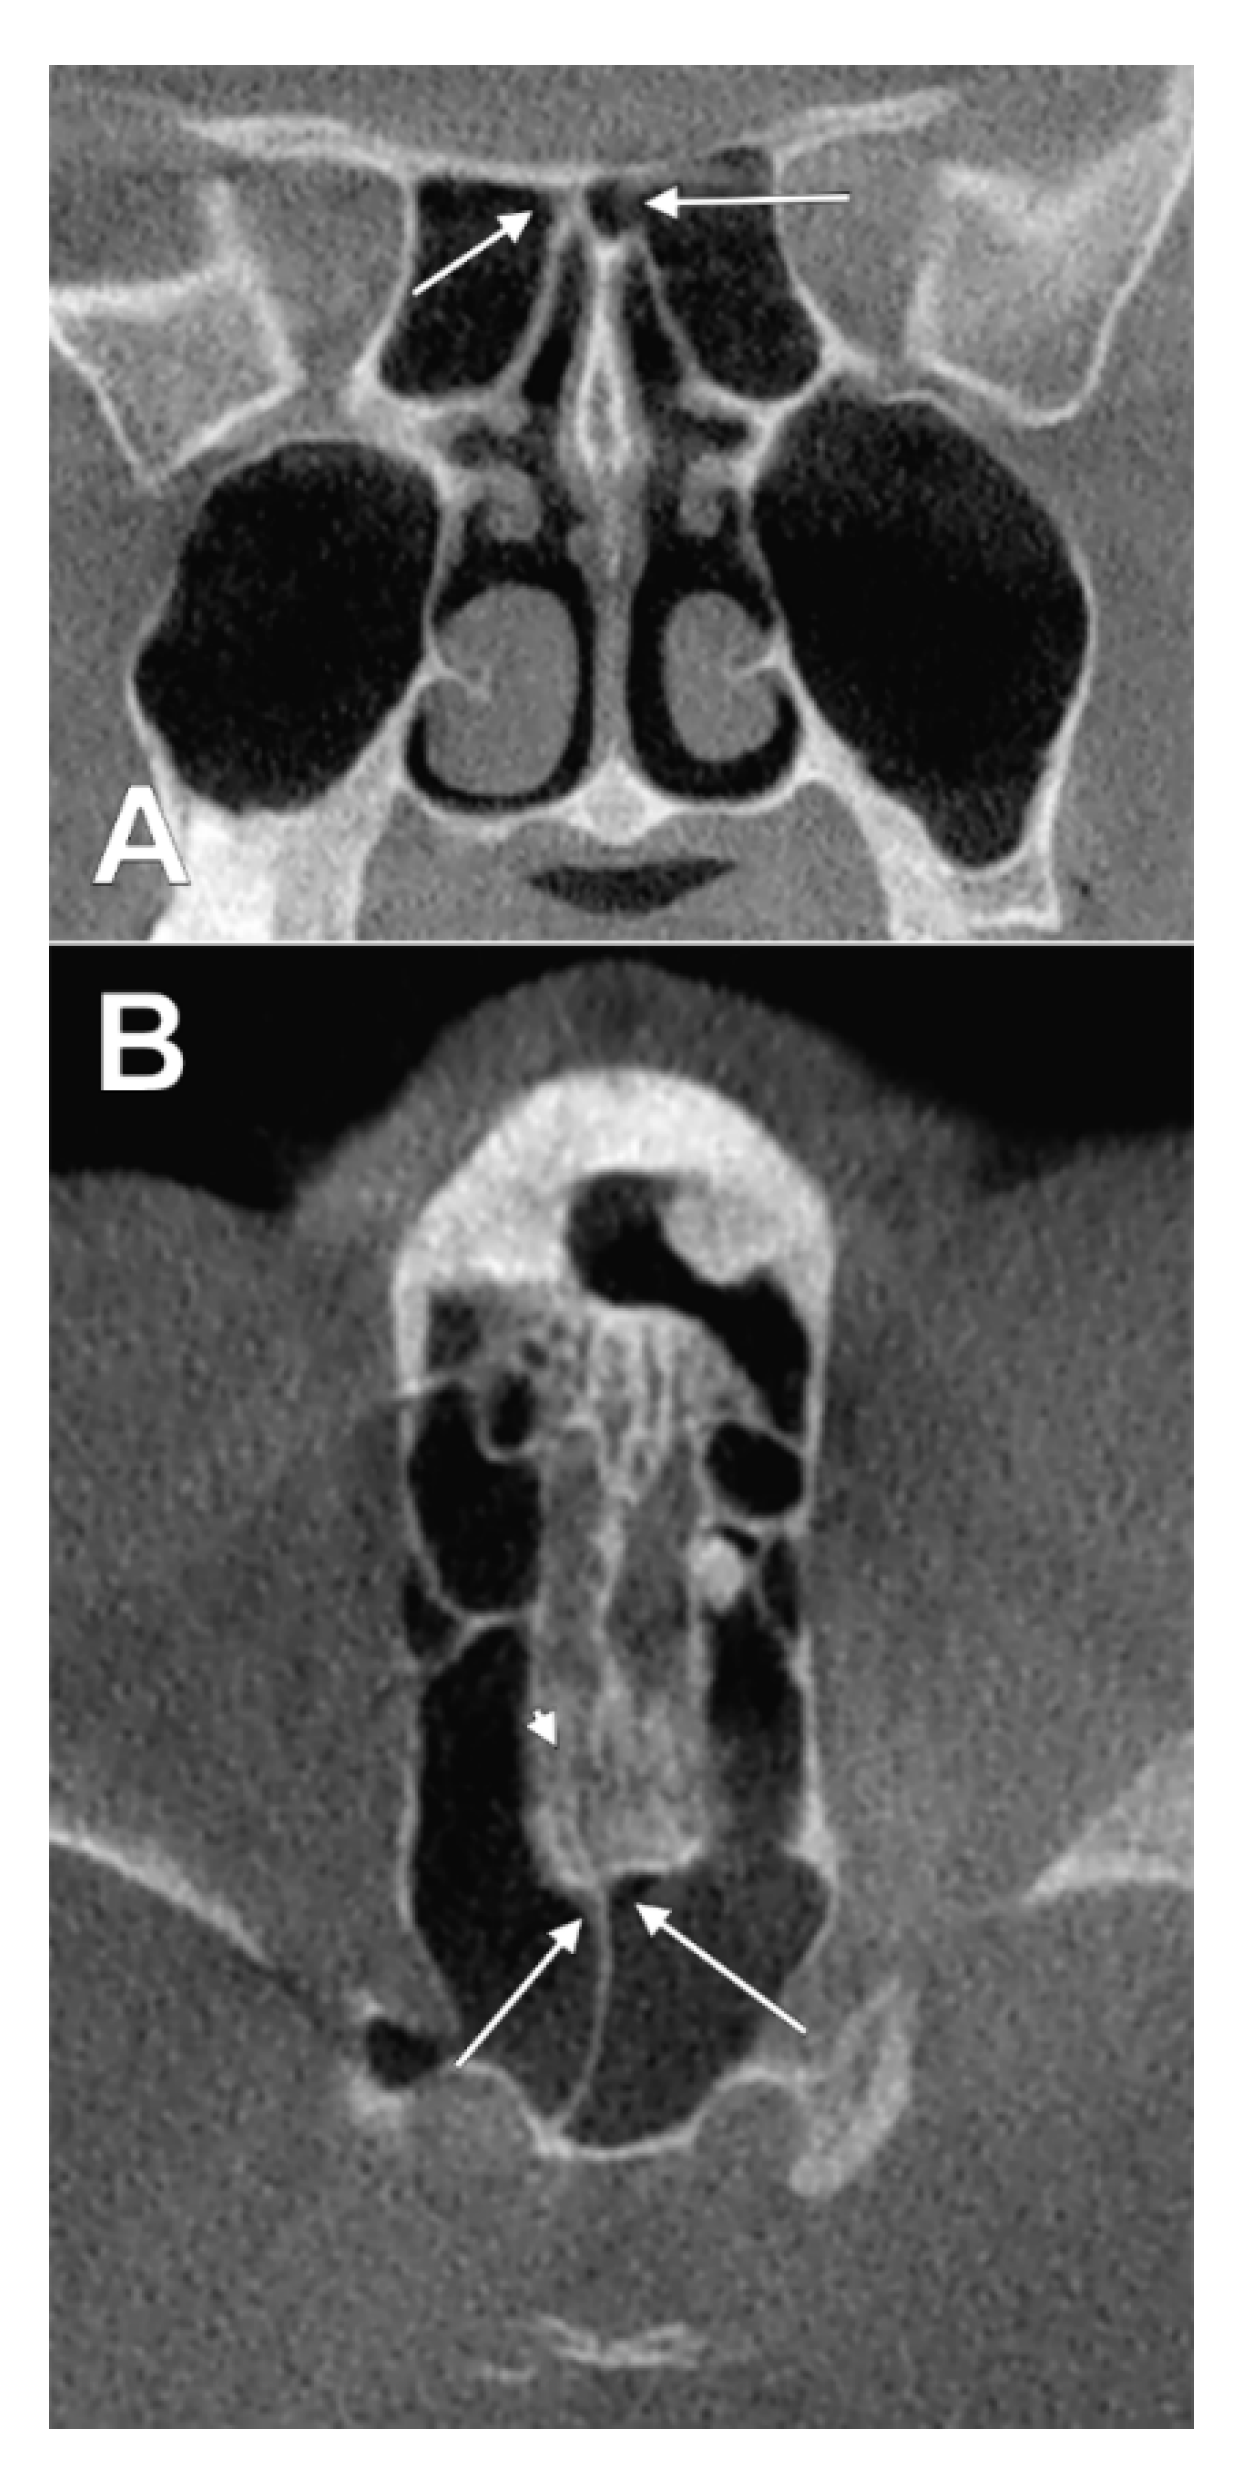

3.3. Sphenoethmoidal (Onodi Cell) Origin of Nasal Roof Pneumatizations

4. Discussion

4.2. Ethmoidal and Sphenoidal Pneumatizations

4.3. Clinical Anatomy